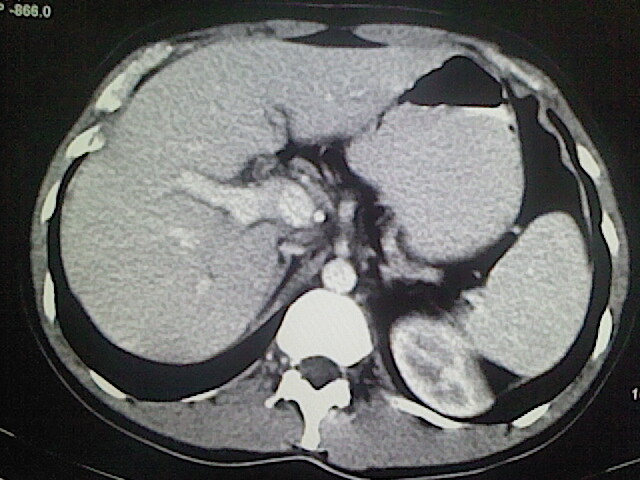

以下是引用卜一在2009-3-14 9:49:00的发言:[br]胆囊萎缩,胆囊壁不规则增厚,内部结构模糊,增强明显强化。另:肝左叶外侧段肝囊肿。支持:慢性胆囊炎!高度可疑:胆囊癌!

以下是引用余辉在2009-3-14 8:48:00的发言:[br]1)慢性胆囊炎。2)肝左叶外侧段肝囊肿。3)脂肪肝。[br]支持,胆囊萎缩,密度增高,不知b超具体有何提示,钙胆汁?结石?

以下是引用jiangjing在2009-3-14 10:18:00的发言:[br]1)慢性胆囊炎。2)肝左叶外侧段肝囊肿。3)脂肪肝。4.】建议行肝功能检查